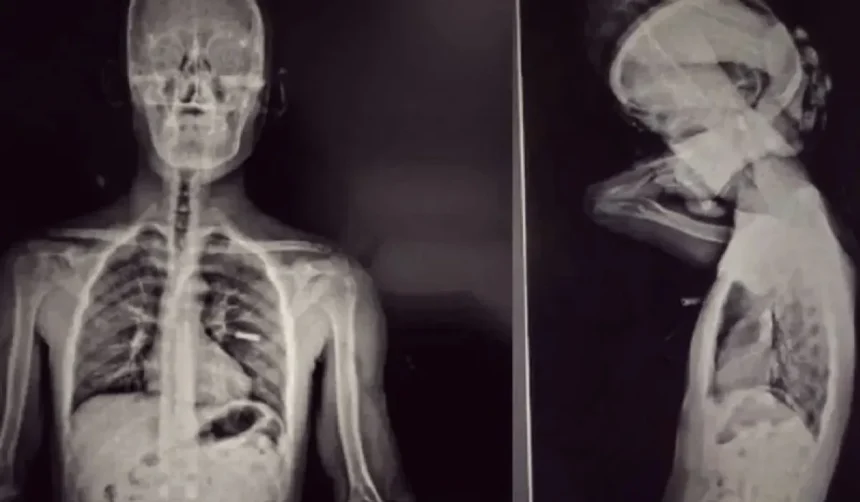

Los sospechosos fueron trasladados al Puente Internacional Horacio Guzmán para someterse a un escáner corporal que reveló la presencia de cuerpos extraños en la zona abdominal. A pesar de que ambos negaron haber ingerido cápsulas de droga, se dio intervención inmediata a la Unidad Fiscal Federal de Jujuy. Posteriormente, fueron internados bajo custodia en el Hospital Jorge Uro de La Quiaca, donde los estudios radiológicos confirmaron sin lugar a dudas la existencia de los elementos en sus organismos.

Horas después de la internación, los detenidos evacuaron un total de 192 cápsulas que contenían cocaína, siendo 96 cápsulas por cada persona. El peso total de la sustancia incautada alcanzó los 2.218 gramos, lo que representa más de un kilogramo transportado por cada individuo. Las pruebas químicas realizadas confirmaron que se trataba de cocaína pura, y el valor estimado de la droga decomisada supera los 47 millones de pesos.